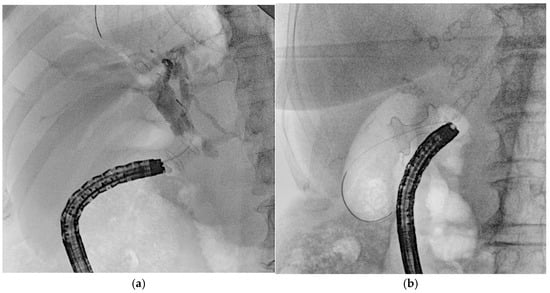

Figure 8. Radiological image of the EUS-PD rendezvous technique. (a) After placing a stent across pancreaticogastrostomy, the guidewire is advanced in an antegrade manner into the pancreatic duct under EUS guidance, followed by standard ERCP and transpapillary stent placement over the wire for pancreatic duct drainage. (b) The end of the procedure with the two stents (highlighted by the red arrows) in the main pancreatic duct.

4.2. EUS–Pancreatic Drainage (EUS-PD)

Two main approaches for EUS-PD exist: EUS-Rv, where a small-caliber wire is advanced in an antegrade manner into the duodenum for ERCP stenting (Figure 8), and EUS-PD transmural drainage, involving serial dilation and stent placement from the stomach or the duodenum (pancreaticogastrostomy/pancreaticoduodenostomy) [50]. Successful EUS-PD relies on precise pancreatic duct puncture and effective guidewire manipulation, given the small duct size, side branches, and potential strictures. A 19-gauge needle with a sharp tip and a 0.025-inch flexible-tip guidewire is generally recommended [51]. In cases with a small pancreatic duct, a 22-gauge needle combined with a smaller (0.018-or 0.021-inch) guidewire may be used, though these thinner guidewires can be challenging to manipulate even after successful duct puncture [52]. The advantage of the 22-gauge needle lies in its ability to puncture even a fibrotic pancreas or a stiff, narrow MPD; in their single-center retrospective study, Matsunami et al. reported high technical success in EUS-PD using a 22-gauge needle despite targeting a small MPD (median diameter 3.5 mm, range 1–14 mm) [53]. However, due to the limited fluoroscopic visibility and insufficient shaft stiffness for therapeutic device support that 0.018- and 0.021-inch guidewires typically offer, when initial access is achieved with a smaller guidewire, a subsequent exchange to a larger-caliber (0.025- or 0.035-inch), stiffer wire is often necessary to ensure procedural success [54]. Studies such as those by Inoue et al. [55] and Sasaki et al. [56] have noted the value of an ultra-tapered or hybrid wire with a stiff body to facilitate pushability and a soft tip to minimize ductal trauma. For patients with surgically altered anatomy, such as those who have undergone gastrectomy, selecting an appropriate puncture site can be difficult due to the reduced stomach volume. In such cases, transjejunal EUS-PD is an ideal approach, as the jejunum and pancreatic duct are closely anastomosed. A stiff guidewire, typically used for endoscopic long intestinal tube insertion, helps optimize this technique. After straightening the twisted afferent jejunal loop using an enteroscope, the guidewire is placed to maintain the loop’s shape. Additionally, by deploying the guidewire into the working channel of a forward-viewing echoendoscope (ropeway method), smooth scope insertion is achieved, facilitating the transjejunal EUS-PD procedure [57].